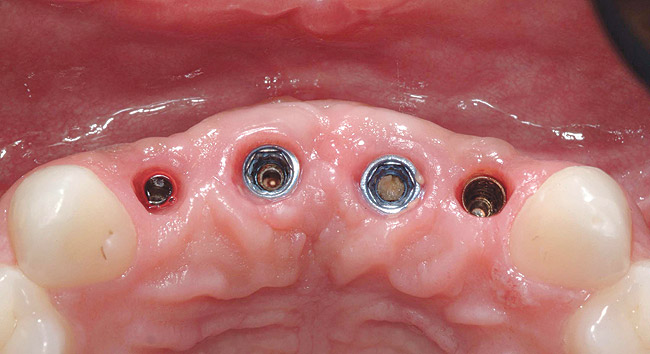

Figure 3  Occlusal view of four anterior mandibular implants. Two of the retaining screws fractured and remained inside the corresponding abutment screws (left). The abutment screw in the left anterior implant fractured, with the apical portion of the screw remaining inside the implant (center).

Figure 3